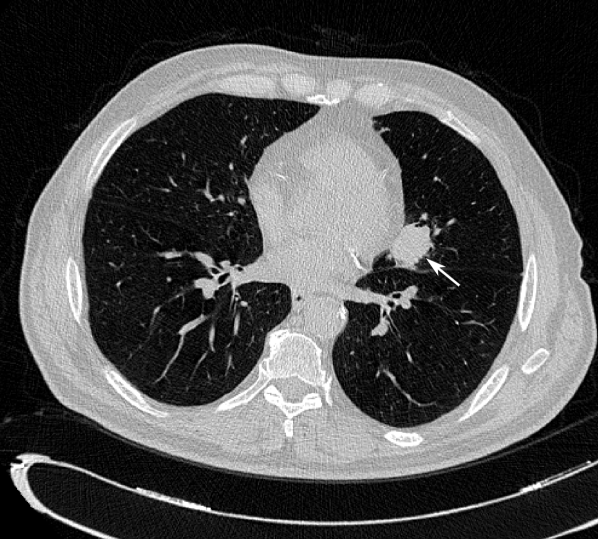

Each CT scan was read by at least one radiologist at CHUSJ to identify pulmonary nodules and other suspicious lesions. A total of 5 radiologists with at least 4 years of experience reading up to 30 CTs per week, hereinafter referred to as R1 to R5, participated in the annotation process. Annotations were performed in a single blinded fashion, i.e. a radiologist would read the scan once and no consensus or review between the radiologists was performed. Each scan was read by at least one radiologist. The instructions for manual annotation were adapted from LIDC-IDRI[13]. Each radiologist would read a scan and identify the following lesions: i) nodule \geq3mm: any lesion considered to be a nodule by the radiologist with greatest in-plane dimension larger or equal to 3mm; ii) nodule <<3mm: any lesion considered to be a nodule by the radiologist with greatest in-plane dimension smaller than 3mm; iii) non-nodule: any pulmonary lesion considered not to be a nodule by the radiologist, but that contains features which could make it identifiable as a nodule. Figure 1 show examples of annotated lesions in LNDb.

Figure 1: Examples of annotated lesions. (a) Nodule \geq3mm annotated by 3 radiologists; (b) Nodule <<3mm annotated by 2 radiologists; (c) Non-nodule annotated by 2 radiologists.